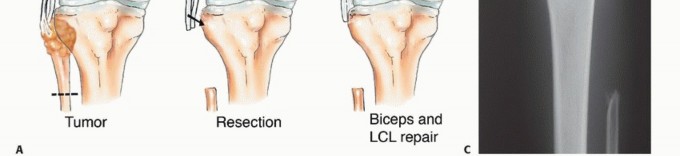

الاستئصال من النوع الأول (Type I Resection):

- الإشارة: يُستخدم لعلاج الأورام الحميدة العدوانية والأورام الغرنية منخفضة الدرجة التي تسببت في تدمير قشري كبير للشظية القريبة.

- الإجراء: يشمل إزالة الشظية القريبة، وغلاف عضلي رقيق من جميع الأبعاد، وموقع ارتباط الرباط الجانبي الوحشي (LCL). يتم الحفاظ على العصب الشظوي المشترك وفروعه الحركية، ويتم استئصال المفصل الظنبوبي الشظوي داخل المفصل.

- الحفاظ: يتم الحفاظ على العصب الشظوي والشريان الظنبوبي الأمامي عادةً.

يوضح الجدول التالي الهياكل التشريحية التي يتم إزالتها مع أنواع الاستئصال المختلفة للشظية القريبة:

| نوع الجراحة | موقع ارتباط الرباط الجانبي الوحشي | الشريان الظنبوبي الأمامي | العصب الشظوي |

|---|---|---|---|

| الكشط | سليم | سليم | سليم |

| استئصال من النوع الأول | مُزال | سليم | سليم |

| استئصال من النوع الثاني | مُزال | مُزال | مُزال |